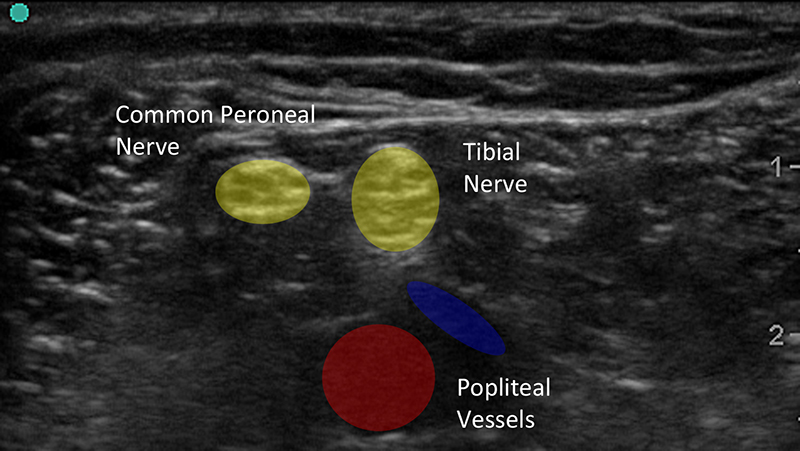

Figure 1b. Ultrasound Image of Peripheral Nerves With Labels

- Classically, nerves have a honeycomb-like appearance in cross section caused by bundling of hypoechoic nerve fascicles within hyperechoic peri- and endoneurium.

- Distal or smaller nerves contain smaller amounts of myelinated axons and can instead look like the cut end of a rope and mimic the appearance tendons.

- Nerves may be oval, round or triangular and often change shape along their course.

- Nerves are often found by their association with more easily identified structures such as blood vessels, bone or muscles.